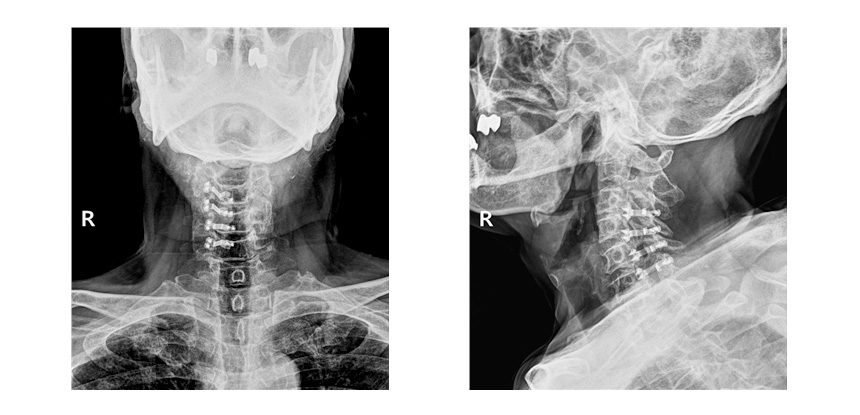

후궁성형술을 시행한 사진